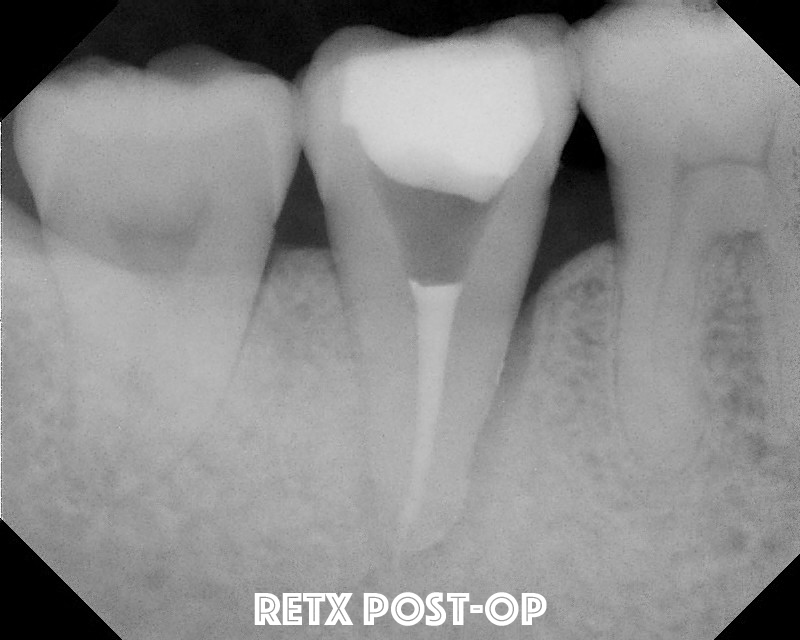

Unfortunately, at the 2 year re-evaluation, the lateral lesion did not resolve. Since I'm working on a periodontist friend of mine, why not try a retreat again?  We tried it and again found no root fracture, or obvious reason for the failure to heal.

Four years later at another re-evaluation, the bone loss on the lateral is even worse. We are still puzzled at why this has not resolved, but not convinced there is a root fracture, so we decided to try intentional replantation.   So, here are some of the best photos I have to document the process.

A seven year recall finds tooth #31 asymptomatic and fully functional.  While the mesial bone looks irregular, there is no periodontal pocket.  If you look at the initial photo of the extracted tooth, you can see the periodontal ligament, but there appears to be an area where the ligament had been lost.  There was not visible fracture on that area of the root at that time.  My assumption is that the pdl may not have ever reformed in that area - causing the current radiographic appearance. It is interesting how a perfectly good root canal and retreatment failed to give the desired results, but a last ditch effort with replantation has been successful up to this point.